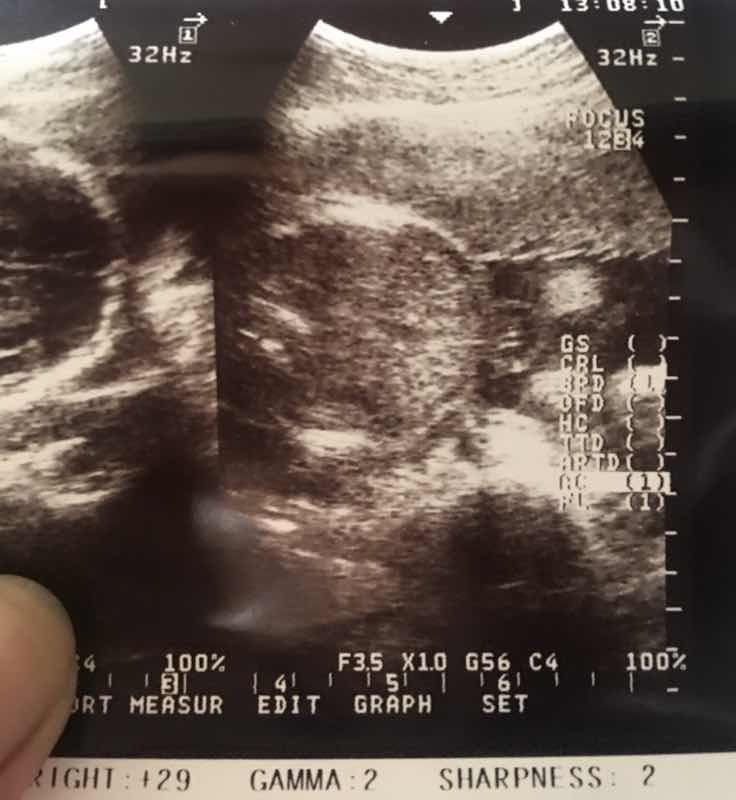

Face po ba ito ng baby?

Hindi po :) ganyan din itsura nung sinukat yung tyan ng baby ko hehe

I think hindi po.